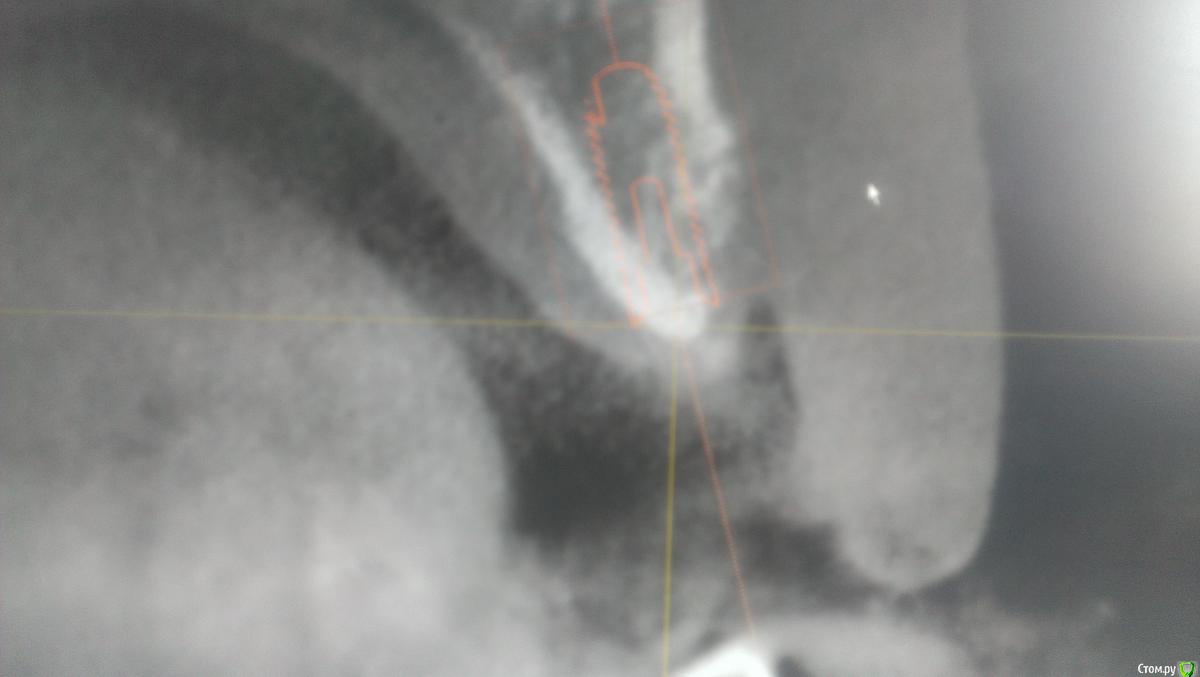

AlexFox Опубликовано 13 июля, 2016 Поделиться Опубликовано 13 июля, 2016 Доброго времени суток,коллеги.Огромная просьба к имплантологам поделиться своим мнением по-поводу клинического случая.Пациенту 45 лет,жалобы на отсутствие жевательной группы зубов во втором сегменте.Для постановки имплантов требуется синуслифтинг.Меня настораживает малый объем имеющейся костной ткани при большом объеме поднятия дна.Плюс слизистой на кт я вообще не вижу.Хотелось бы узнать ваше мнение об этом. Ссылка на комментарий

BugDan Опубликовано 14 июля, 2016 Поделиться Опубликовано 14 июля, 2016 (изменено) Я бы сделал синус с ауто-ксено 1:1 по причине чистой кортикалки в области моляров.Ставить ли импланты сразу или нет зависит от макродизайна имплантатов котрыми вы планируете пользоваться и опыта в первую очередь.На картинках планирования 23 стоит далековато от 22 , винт 5 стоит чуть медиальнее чем надо, а 6 сильно медиальнее чем нужно. Для страховки просмотрите латеральную стенку синуса на предмет артерии. Изменено 14 июля, 2016 пользователем BugDan Ссылка на комментарий

Zborzh Опубликовано 14 июля, 2016 Поделиться Опубликовано 14 июля, 2016 Хотя бы пару винтов с синусом поставьте, хоть какая то поддержка для графта будет. Третий винт, дистальный, месяцев через 5 можно доставить. Старайтесь выбирать имплантаты с активной резьбой, типа SPI или Nobel active. При условии их использования и грамотной модификации протокола сверления, может, и все 3 имплантата получится зафиксировать. Ссылка на комментарий